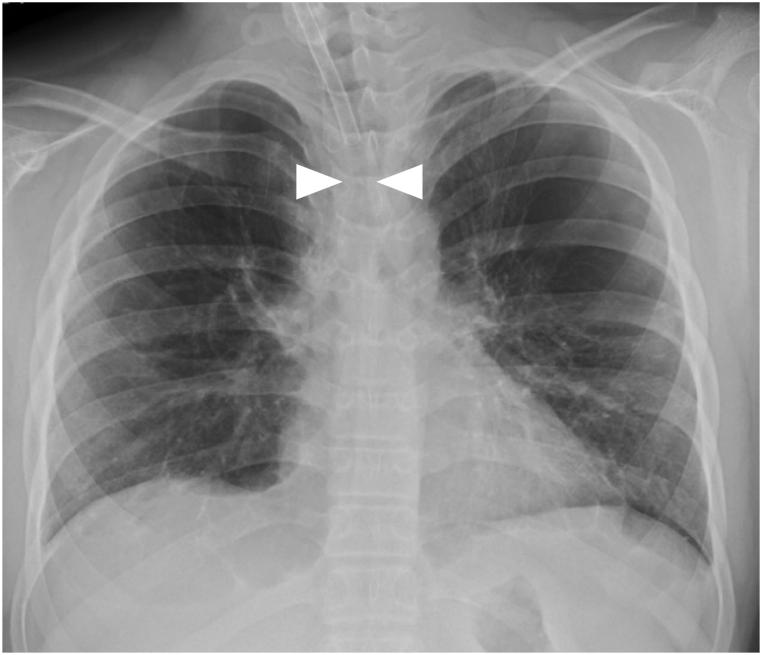

A 14-year-old boy presented to our pediatric department with epilepsy and psychomotor retardation. He was born at 24 weeks and 4 days of gestation and weighed 705 g at birth. He underwent a tracheostomy for tracheomalacia at 1 year of age. At the age of 12 years, granulation formed at the tip of the tracheostomy cannula, resulting in severe tracheal stenosis, which was repeatedly managed using ventilator management and replacement cannulas. As bronchoscopic cauterization and removal of the granulation tissue did not improve the condition, triamcinolone acetonide solution was injected into the granulation tissue three times, which resulted in regression of the granulation. Thereafter, no restenosis has been observed for more than 8 years.

一名14岁男孩因癫痫和精神运动发育迟缓就诊于我院儿科。他出生时孕周为24周4天,出生体重705克。1岁时因气管软化接受气管切开术。12岁时气管切开插管尖端形成肉芽组织,导致严重气管狭窄,多次采用呼吸机管理和更换插管进行处理。由于支气管镜烧灼和切除肉芽组织未能改善病情,遂向肉芽组织内注射曲安奈德溶液3次,肉芽组织消退。此后,8年多未观察到再狭窄。